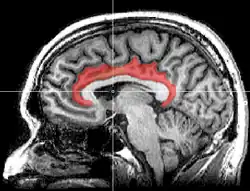

![]() Medial surface of left cerebral hemisphere, with cingulate gyrus, and cingulate sulcus shown in red. | |

The cingulate cortex is a part of the brain situated in the medial aspect of the cerebral cortex. The cingulate cortex includes the entire cingulate gyrus, which lies immediately above the corpus callosum, and the continuation of this in the cingulate sulcus. The cingulate cortex is usually considered part of the limbic lobe.